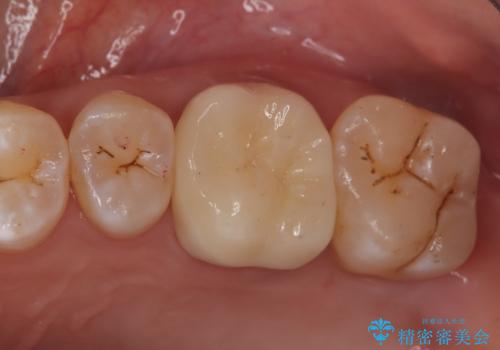

検査で見つかった虫歯 セラミッククラウンでの治療

担当医 岡田康成